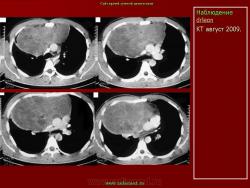

НАБЛЮДЕНИЯ КОЛЛЕГ

1.

2.